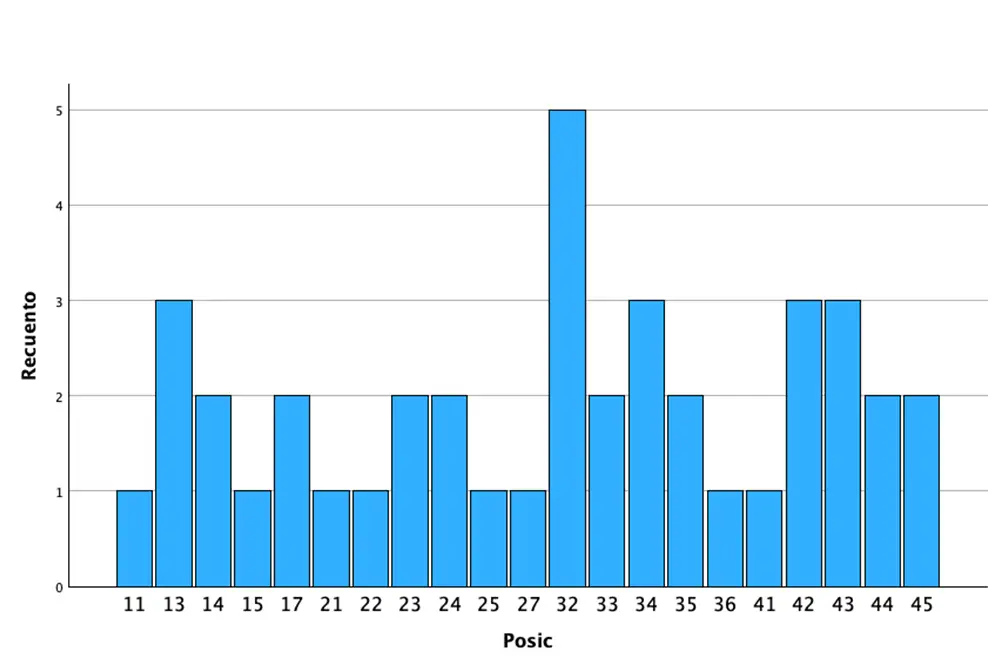

Fueron reclutados 9 pacientes en los que se insertaron 41 implantes que cumplieron con los criterios de inclusión anteriormente descritos. La edad media fue de 68,77 años (+/- 6,69) y 6 de los 9 pacientes eran de sexo femenino. De los 41 implantes, el 41,5% se insertaron en el maxilar superior, siendo la posición más frecuente para esta área anatómica la correspondiente al diente 13 (7,3%) y el 58,5% en la mandíbula, siendo la localización más frecuente en esta área para la pieza 32 (12,2%). Todas las localizaciones analizadas se muestran en la figura 1. En cuanto a las dimensiones de los implantes, el diámetro osciló entre los 2,5 y los 3,5 mm, siendo el más frecuente 3,30 mm en el 53,7% de los casos. La longitud de los implantes fue de 5,5 mm en el 36,6% y de 6,5 mm en el 63,4%. Todas las longitudes y diámetros en función de la posición del implante se detallan en la figura 2.

Figura 1. Posiciones de los implantes incluidas en el estudio.

Figura 1. Posiciones de los implantes incluidas en el estudio.